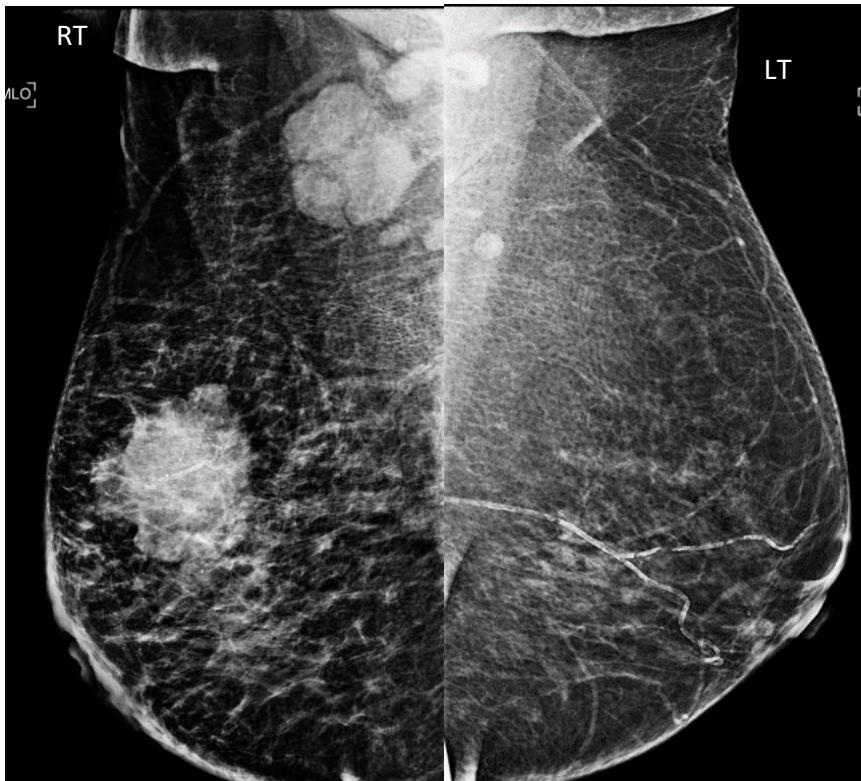

Dr. Sana Shaikh et al. Axillary Nodal Metastases – Prediction by Ultrasound and Digital Mammogram Features of Primary Breast Malignancy